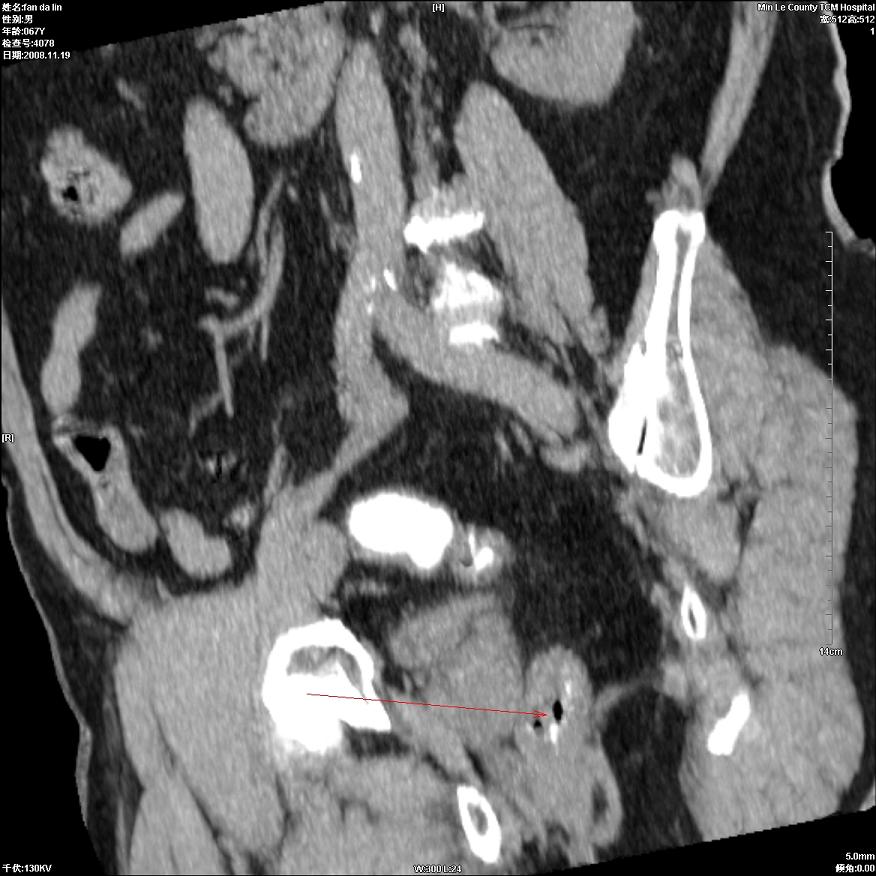

标题: CT16698:M67Y,看看直肠下端是不是病变 [打印本页]

标题: CT16698:M67Y,看看直肠下端是不是病变

粘膜皱壁,不除外内痔

直肠及乙状结肠管壁均增厚,考虑炎症.

直乙交界处肠壁不规则增厚,还是做个肠镜吧

只是肠壁局限性增厚,但难说明问题。